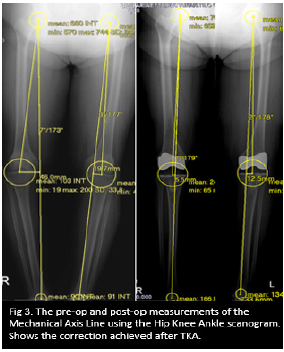

Using Hip- knee -ankle scanogram radiograph, corrected mechanical axis alignment was measured. Using lateral knee X-ray femoral and tibial component alignment was measured and using the skyline view the patellar tracking was measured. The femoral mechanical axis angle (FMA), Mechanical axis deviation angle (MAD) and the distance of Mechanical axis deviation (mm) from the center of the knee were all measured as showed in the Figure1-3.

Figure 1: Using KPACS tool round ROI, locating the center of the femoral head, knee and ankle joint.

Figure 2: With the centers defined, measurement of the Femoral Neck Shaft Angle (FNSA), Femoral Mechanical Axis Angle (FMAA), Mechanical Axis Deviation angle (MAD) and the displacement (mm) of the mechanical axis line from the center of the knee joint.

Figure 3: The pre-op and post-op measurements of the Mechanical axis line using the hip knee ankle scanogram. Shows the correction achieved after TKA.